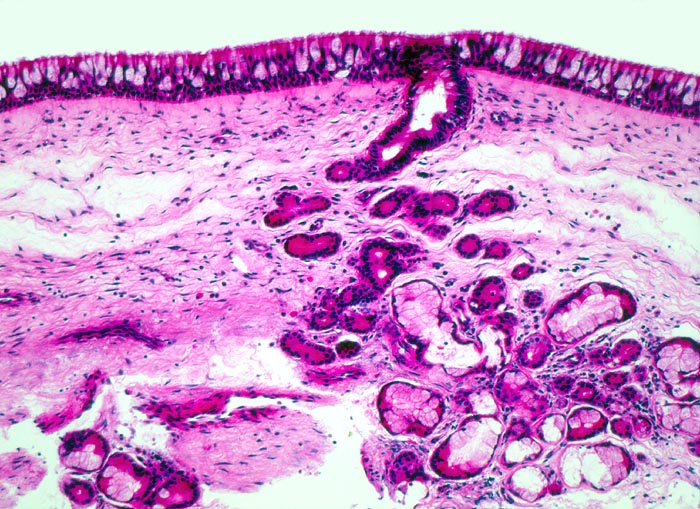

respiratorisches Epithel: Nasennebenhöhlenschleimhaut

Sinus ethmoidalis

Relativ dichtes weitgehend entzündungsfreies subepitheliales Stroma mit seromukösen Schleimdrüsen. Die Mukosa besteht aus einem mehrreihigen Epithel mit Flimmerzellen und Becherzellen.